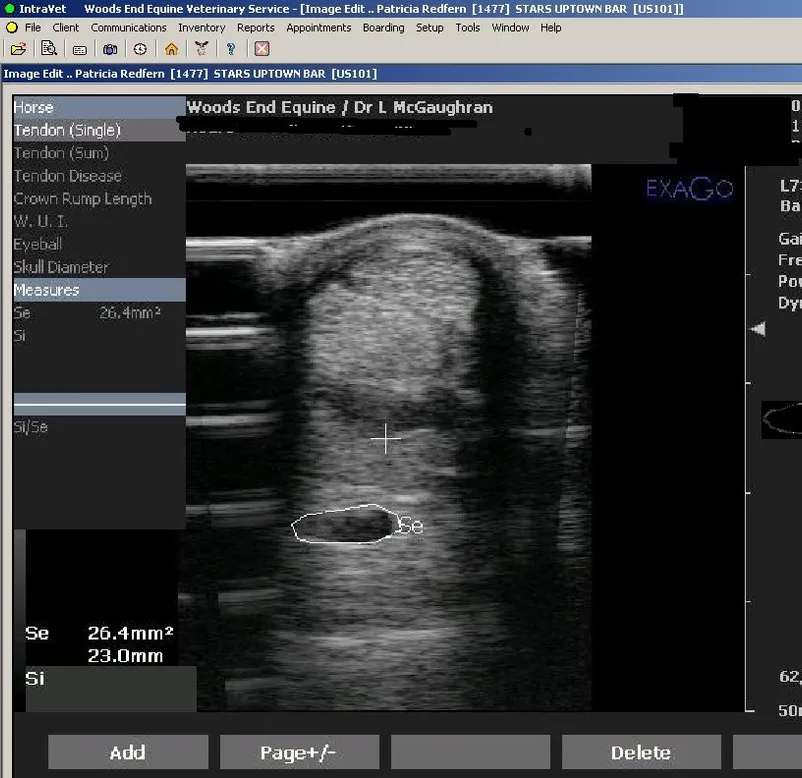

Ultrasound Imaging

Ultrasound imaging involves using sound waves to create an image on a monitor. When the wand passes over an injured area of your horse, we are able to find hidden problems like joint, tendon, muscle and ligament injuries. Also detect tumors, cysts, and abscesses on certain area of the horse. Most importantly discover any late pregnancies or twins. Ultrasound imaging is completely painless and does not have any side-effects.